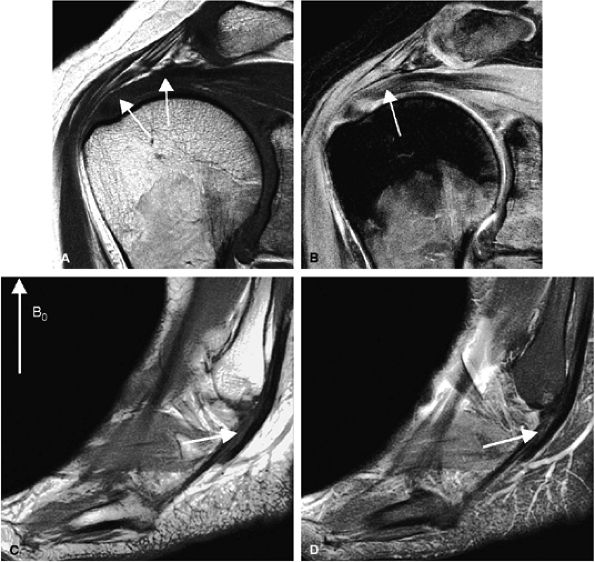

FIGURE 1.4 ● Magic angle effect (arrows). (A, B) Magic angle is seen in a shoulder examination using a short TE (A) and long TE (B). Magic angle in an ankle examination without (C) and with (D) FatSat.